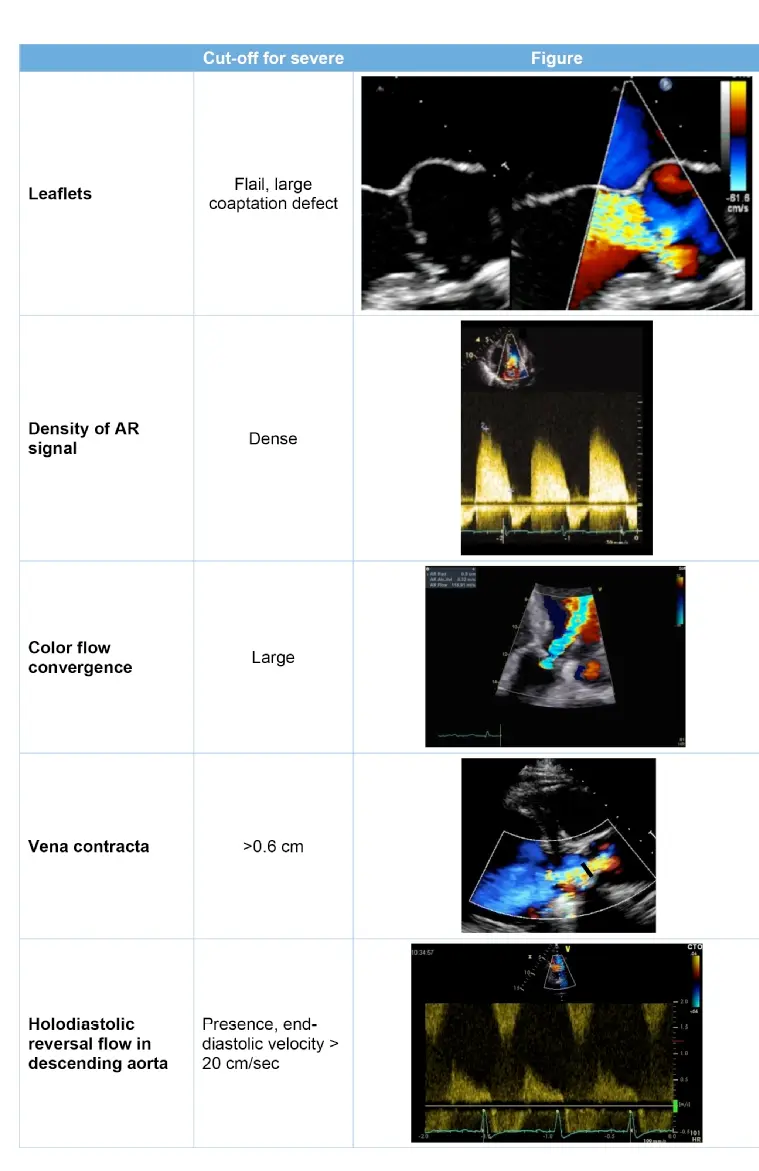

Vena Contracta Width

- A VC < 0.3 cm indicates mild, 0.3-0.6 cm indicates moderate, and > 0.6 cm indicates severe AR.1

CWD

- Measurement of the AR peak velocity and VTI by CWD allows calculation of the EROA and RVol

- The threshold for severe AR is an EROA ≥0.30 cm^2 and an RVol > 60 mL

PWD

- PWD: Holodiastolic flow reversal is an abnormal finding and indicates at least moderate AR; when present in the abdominal aorta, it is consistent with severe AR.

- Holodiastolic reversal (flow throughout diastole) strongly suggests moderate to severe AR

- End-diastolic velocity: a value >20 cm/s in the descending aorta often suggests severe AR, correlating with an aortic regurgitant fraction ≥ 40%